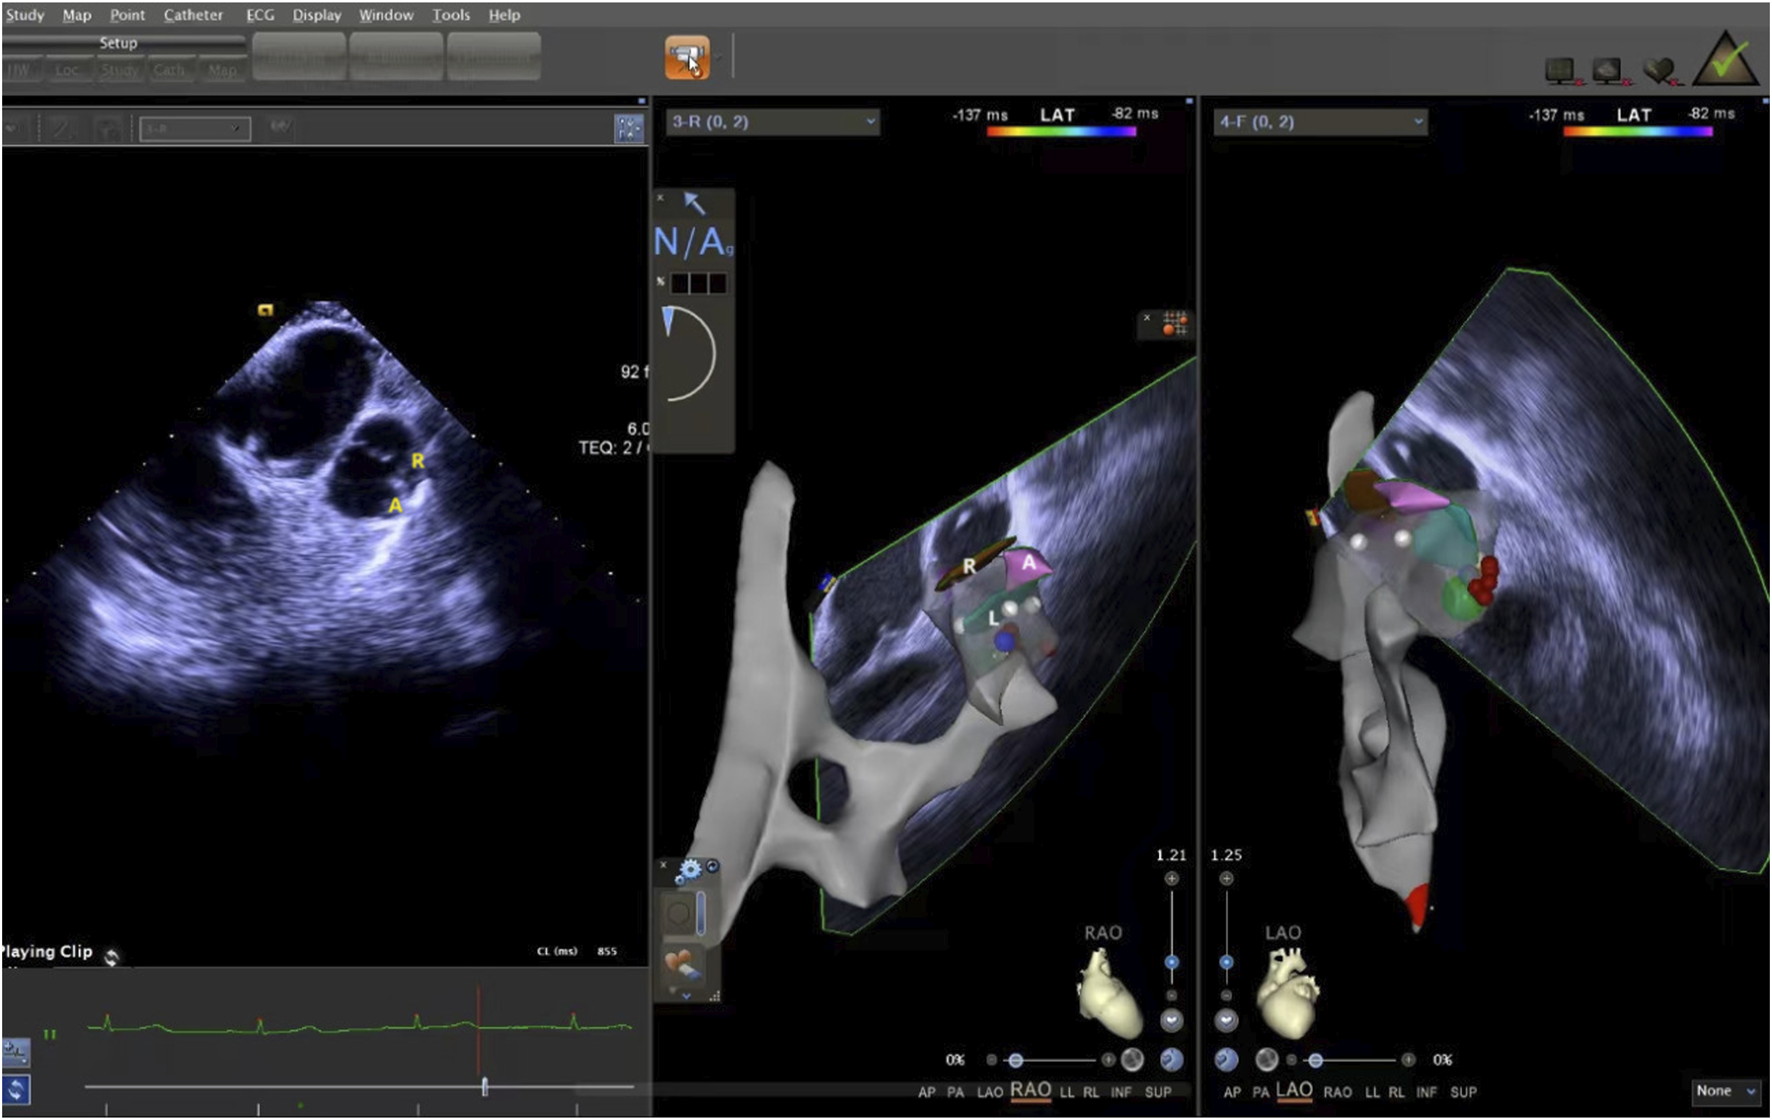

The ICE catheter can be manipulated in multiple directions and angles, allowing for a clear view of all anatomical structures within the cardiac chambers (De Sensi et al., 2021). Advancing the ultrasound catheter with either clockwise or counterclockwise rotation enters the primary field of view of the ICE catheter. This view displays the right atrium (RA), the tricuspid annulus, the aortic sinuses (non-coronary and right coronary), the right ventricular inflow tract, and the outflow tract. By advancing the catheter slightly forward and rotating it clockwise, a short-axis view of the pulmonary artery is achieved. This view reveals the specific positions of the three pulmonary sinuses. In this view, the left pulmonary sinus is closest to the aortic root, while the anterior pulmonary sinus is the farthest from it, positioned superficially next to the pericardium. The right pulmonary sinus is situated slightly to the right of the left pulmonary sinus. Further manipulation of the catheter through the tricuspid annulus into the right ventricle (RV) provides a long-axis view of the pulmonary artery, clearly delineating the RVOT and the pulmonary valve (Figure 5). Collectively, these three views offer a detailed visualization of the pulmonary valve and the three pulmonary sinuses. They also illustrate the junctional regions between the sinuses in the short-axis view (Figure 6).

Figure 5. ICE was used to observe the long-axis section of the right ventricular outflow tract. ICE, Intracardiac echocardiography.

Figure 6. ICE was used to observe the short-axis section of the pulmonary sinus. ICE, Intracardiac echocardiography.